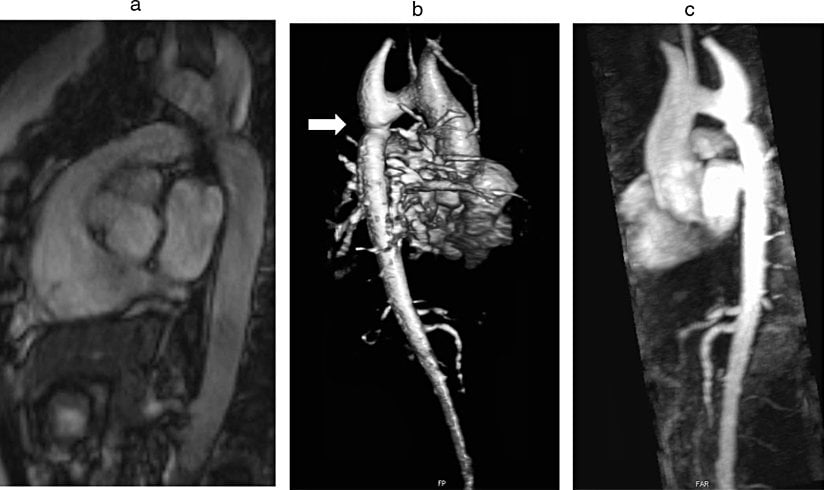

Turner Sendromunda kalp kusurlarının nadir fakat potansiyel olarak ölümcül bir komplikasyonu, aort damarının farklı sebeplerle yırtılması ve duvar içine kan dolmasıyla oluşan aort diseksiyonudur. Aort değerlendirmesi için iki ana görüntüleme tekniği vardır:

- Transtorasik Kardiyak Ekokardiyografi (TTE): Maliyet ve bulunabilirlik açısından avantajlı olsa da, muayenenin konjenital kalp hastalıkları konusunda eğitimli bir klinisyen tarafından yapılması gereklidir. Ayrıca, özellikle bebeklik döneminde muayene sırasındaki hareketlere bağlı torasik hipotez ekojenite ve artefaktlar TTE'nin sık görülen bir dezavantajıdır.

- Aort Manyetik Rezonans Görüntüleme (MRI): Manyetik rezonans görüntüleme, operatöre daha az bağımlıdır ve inen aort dahil tüm aortik ark değerlendirilebilir. Bu teknik, dünya çapında giderek daha fazla kullanılmaktadır.